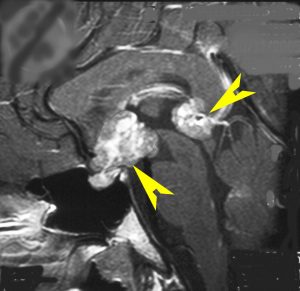

ICE化学療法投与開始から数日で小さくなります

この例は古いので第3脳室開窓術 ETV をしていません。左はICE化学療法前。中央は9日後。右は25日後です。閉塞性水頭症があっても1週間くらいで中脳水道が通って水頭症は改善します。ジャーミノーマであれば,ICE化学療法1コースでかなり縮小するはずです。このような顕著な効果がない時には,逆にジャーミノーマ以外の胚細胞腫瘍が混在していると考えた方がいいでしょう。多くは奇形腫の混在です。

軽度の複視のみで発症した20代前半男性です。右上のように松果体腫瘍の前に割れ目が入るように第3脳室があり,両側視床に浸潤するために軽度の視床浮腫があり,ガドリニウムで強く増強され一部にのう胞があります。これだけでもgeriminomaにかなり特有の所見です。さらに,灰白隆起(矢印)のところに小さな神経下垂体germinoma腫瘍があります (bifocal tumor)。HCGは測定限界以下,AFP 2.5で,水頭症はありません。全ての臨床所見がgerminomaであることを示しています。

生検病理診断をしないでICE化学療法を1コース終えた後の画像です。腫瘍は消失しています。これでgerminomaであることが確認できたので,ICE化学療法を2コース追加して,25.2グレイの全脳室照射をして治療を終了しました。